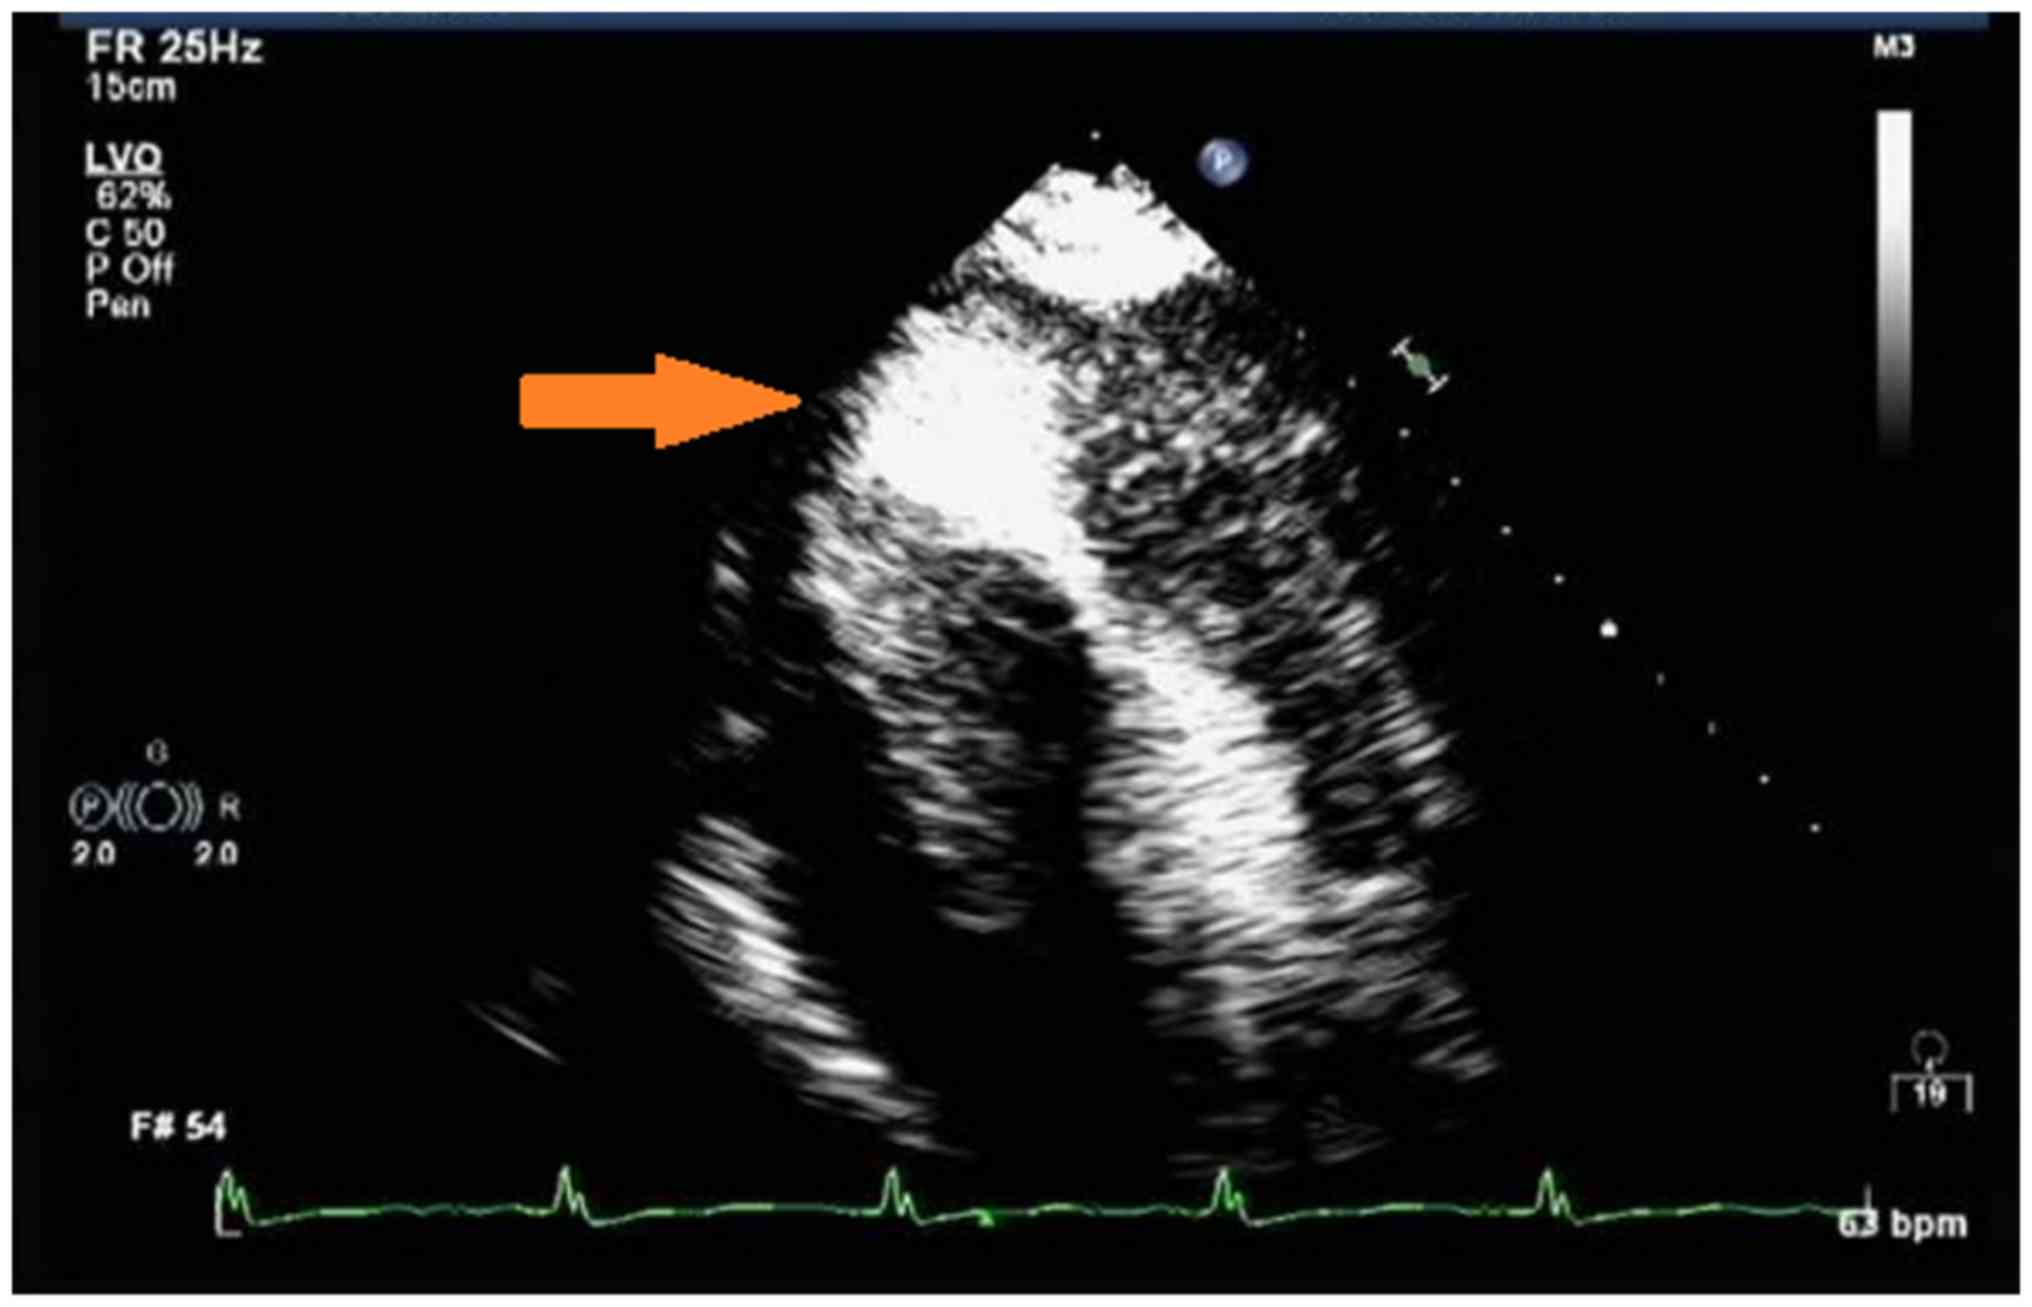

Figure 3.

Transthoracic echocardiography with apical four-chamber view and color Doppler ultrasound on 8th July 2016: Severe hypertrophic cardiomyopathy with mid-cavity obstruction and apical aneurysm was indicated. LA, left atrium; IVS, intraventricular septum.

Figure 4.

Contrast transthoracic echocardiographic image taken on 13th July 2016 demonstrated mid-ventricular narrowing with aneurysmal apex (arrow).